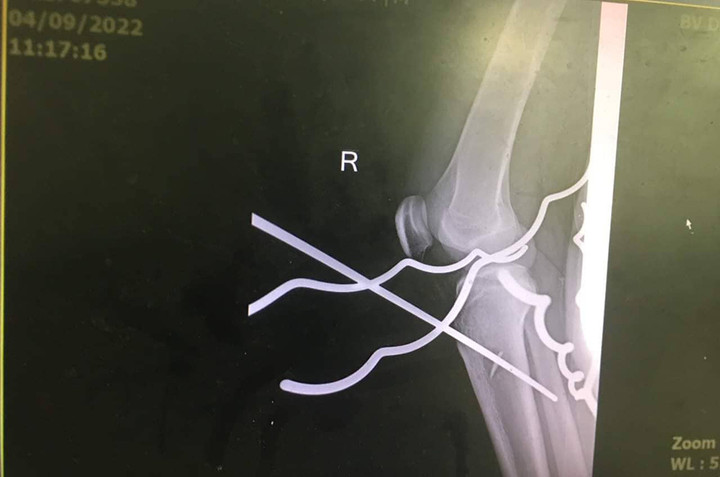

Thanh sắt đâm xuyên chân nam thanh niên. (Ảnh: B.V)

Tại bệnh viện, các bác sĩ nhanh chóng sơ cứu và hội chẩn chuyên khoa Ngoại chấn thương, xử trí cấp cứu cho bệnh nhân. Sau hơn 1 giờ đồng hồ, các thanh sắt được bác sĩ phẫu thuật lấy ra khỏi chân của nam thanh niên. Hiện sức khỏe bệnh nhân ổn định, đang tiếp tục được theo dõi và điều trị tại bệnh viện.

Bác sĩ trực tiếp phẫu thuật cho bệnh nhân cho biết, đây là tai nạn hy hữu, rất nguy hiểm. May mắn bệnh nhân được đưa đến bệnh viện phẫu thuật cấp cứu kịp thời.